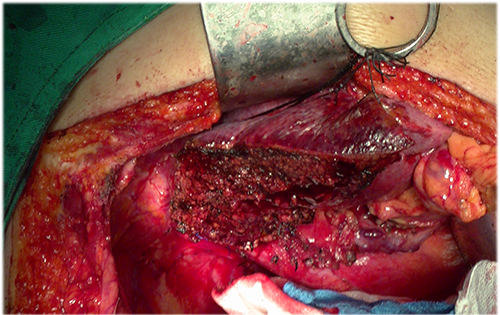

右肝癌、门静脉癌栓----右半肝切除,门静脉癌栓取出术

手术规划--右半肝切除,门静脉取癌栓